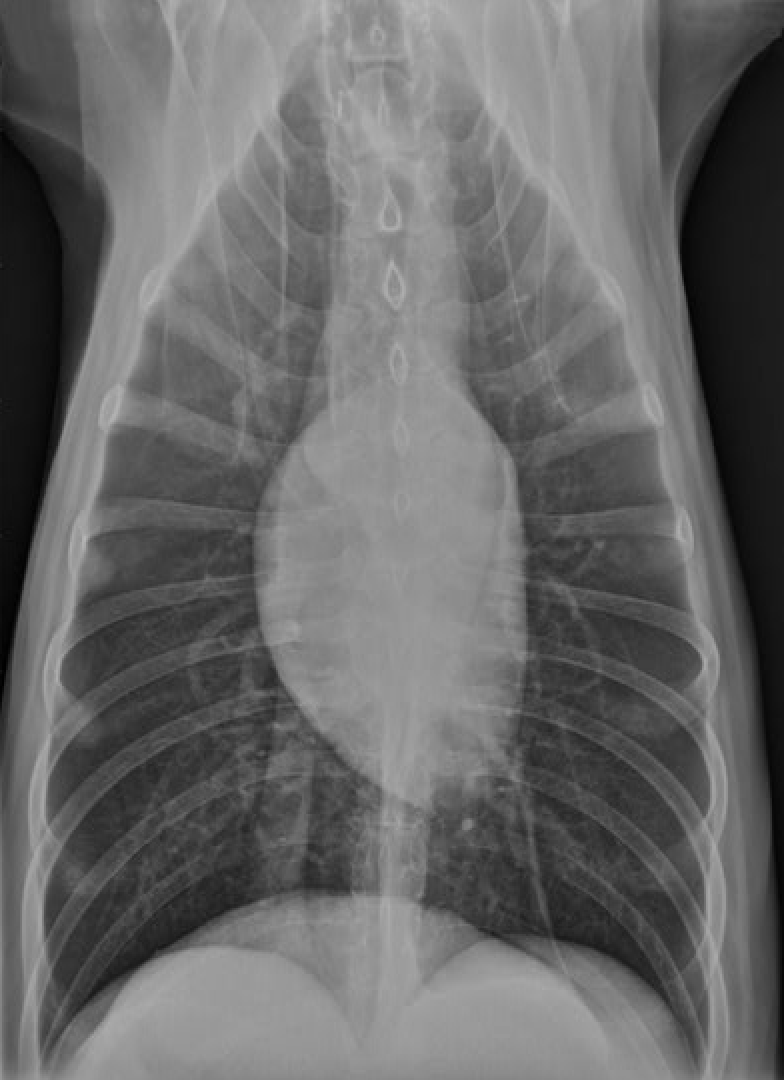

identify the structures

RA: right auricle (atrium)

RV: right ventricle

LV: left ventricle

LA: left atrium

A: aorta

C: caudal vena cava

T: trachea